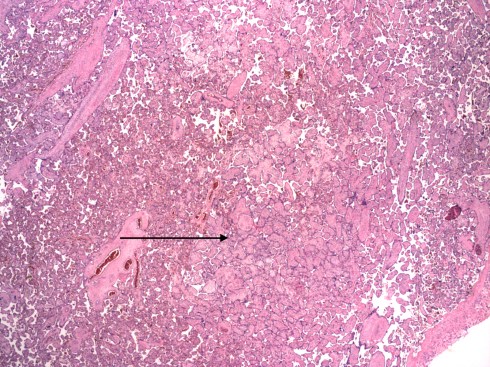

Dr. Sander also described a capillary variant of HEV that occurred in the small end branches of the villous tree. The pathologist can usually spot these areas microscopically at low magnification as slightly edematous and smudged villi (Fig 16a,b).

Fig 16a: This low power of the placental villi demonstrates an area with larger appearing, paler villi (arrow) compared to the surrounding normal villi due to capillary HEV. (H&E, 2x)

Fig 16b: This higher power of the large pale villi. (H&E, 10x)

Higher magnification demonstrates the hallmark lesion of red cells sheared into fragments by their passage through the capillary endothelium and deposited in the loose villous stroma (Fig 17).

Fig 17: This even higher power of villi from the same area as figure 16 shows the blue nuclear fragments of karyorrhexis and fragmented red blood cells. (H&E, 40x)